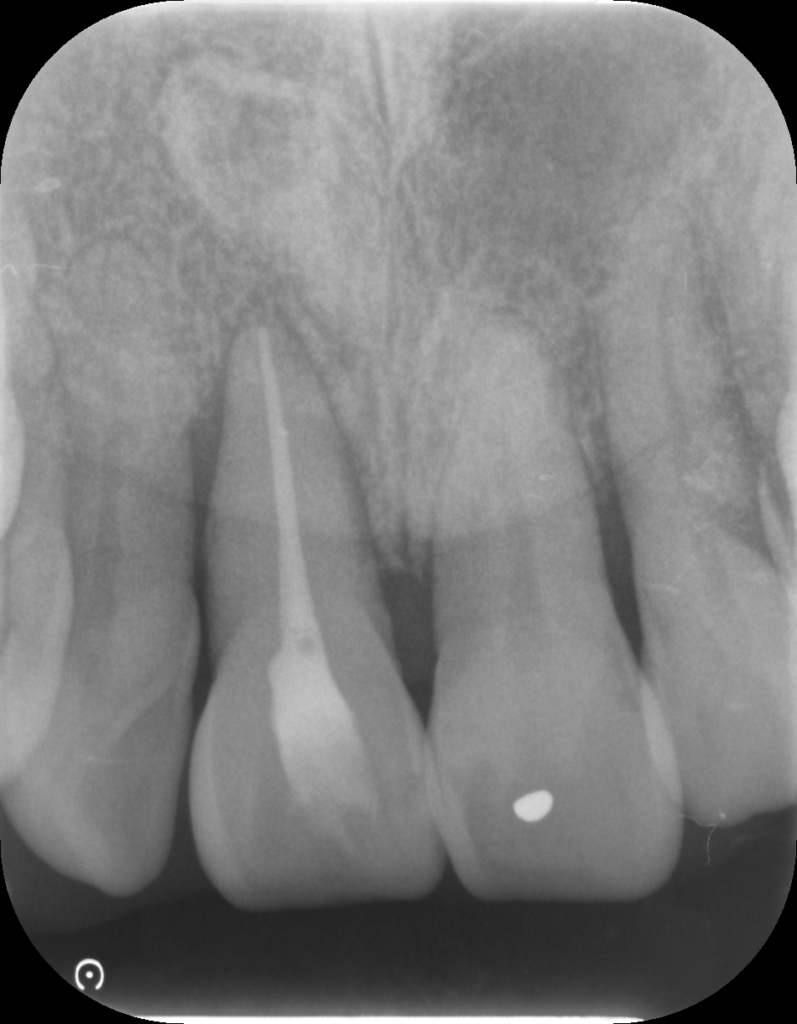

↑治療前後で骨の状態が改善しています。現在は隣の歯と固定して経過を見ています。

↑レントゲンで骨吸収を認めます。歯肉を切開すると実際に骨がありません。